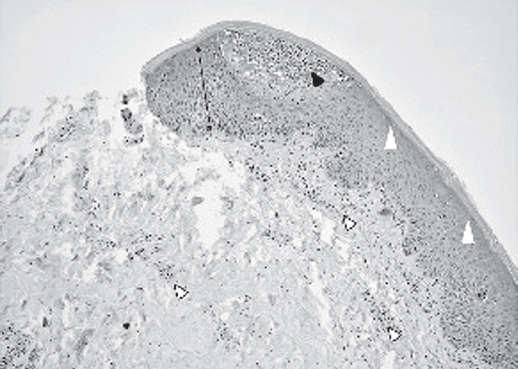

Клинических и лабораторных данных о системном поражении не обнаружено. На основании анамнеза о ранее существовавшем вульгарном псориазе, результатов патоморфологического исследования (рис. 2), выявившего нейтрофильные пустулы и псориазиформные изменения эпидермиса, а также морфологии высыпаний, возникших после отмены глюкокортикостероидов, был установлен диагноз: «Генерализованный пустулезный псориаз, аннулярная форма, тип Milian – Katchoura».

Рис. 2. Микрофотография, окраска гематоксилином и эозином, ×200. В эпидермисе определяется регулярный акантоз (черная двусторонняя стрелка), агранулез (белые треугольники), микроабсцесс Мунро (черная стрелка), в сосочковой и ретикулярной дерме определяется гетерогенный периваскулярный инфильтрат из лимфоцитов, гистиоцитов с примесью нейтрофилов (белые стрелки)

Fig. 2. Micrograph, hematoxylin-eosin staining, ×200. There is a regular acantosis in the epidermis (black double arrowheads), agranulosis (white triangles), Munromicroabscess (black arrow), heterogeneous perivascular infiltrate of lymphocytes, histiocytes with an admixture of neutrophils (white arrows) is determined in the papillary and reticular dermis